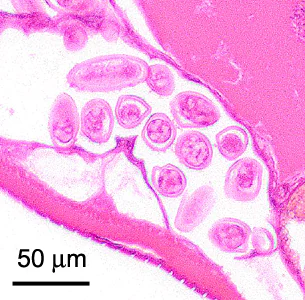

A ten-year-old boy presented at a local hospital with symptoms mimicking an appendicitis. An appendectomy was performed and biopsy specimens were sent to Pathology for routine histologic work-up. Objects suggestive of a parasite were observed by the attending pathologist. Figures A–E show what was observed on a slide stained with hematoxylin-and-eosin (H&E). What is your diagnosis? Based on what criteria?

Figure B